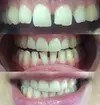

Zirconium Applications

Porcelain Applications

Laminate Veneer